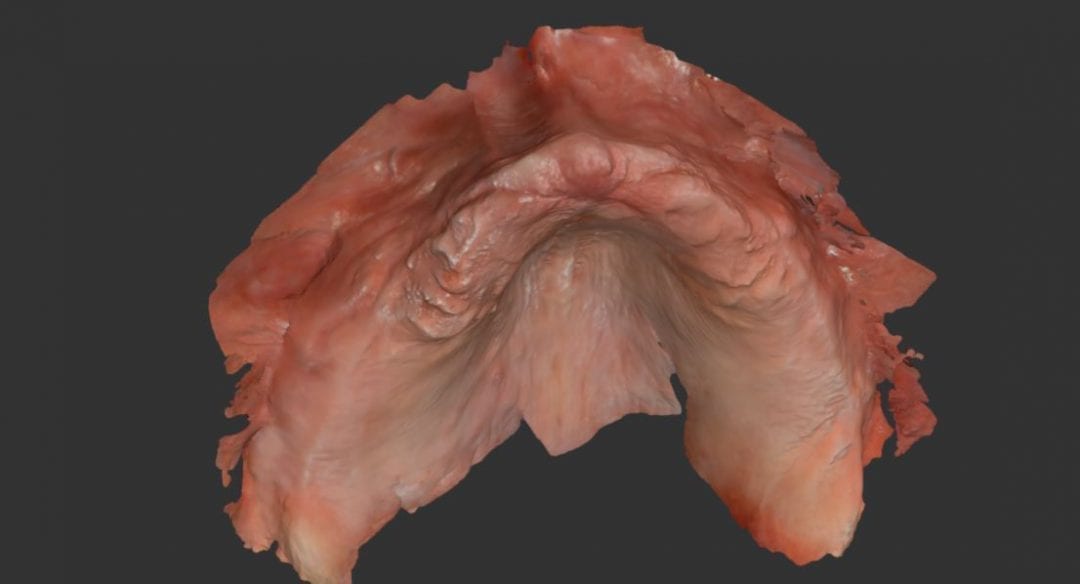

Yes, It Can Scan Edentulous Arches

August 8, 2018A frequent question we receive at CAD-Ray is if the Medit i500 can scan edentulous arches. You can certainly introduce errors in the process, but if you follow proper guidelines, […]

A frequent question we receive at CAD-Ray is if the Medit i500 can scan edentulous arches. You can certainly introduce errors in the process, but if you follow proper guidelines, […]